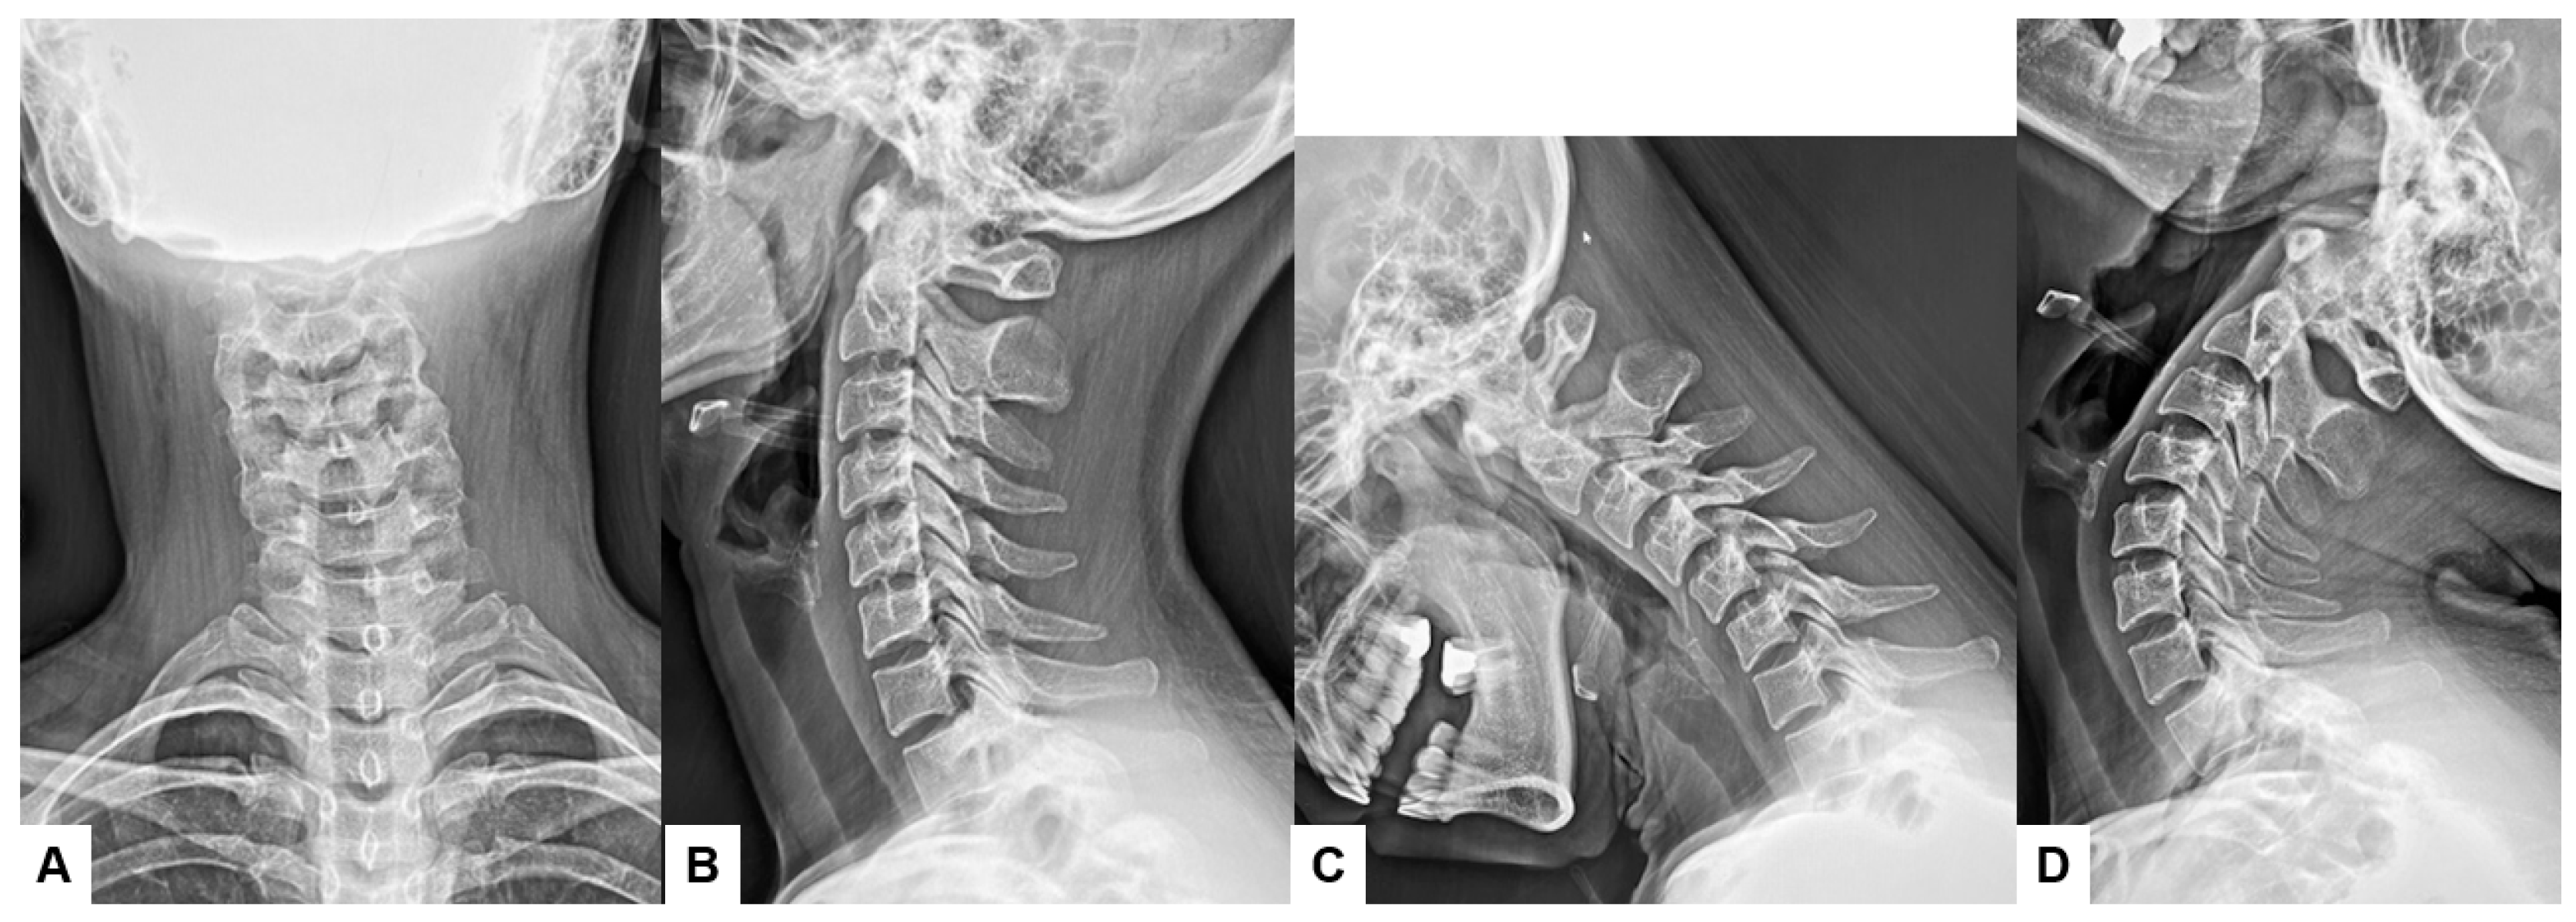

Functional X-rays, which often involve flexion–extension, lateral bending, or other stress maneuvers, provide superior information for determining subtle displacements or intervertebral motion when compared to conventional static X-rays. Therefore, spinal disorders such as spondylolisthesis, segmental instability, or other degenerative changes can be evaluated with dynamic insights [10,11] (Figure 1C,D). Those imaging modalities are widely available in any healthcare setting and relatively inexpensive compared to advanced imaging technologies such as CT and MRI [12].

Figure 1. Thirty-four-year-old F, cervical spondylosis, (A) anteroposterior cervical conventional X-ray, (B) lateral conventional X-ray, (C) lateral flexion X-ray, (D) lateral extension X-ray. Cervical motion is preserved, and there is no instability.